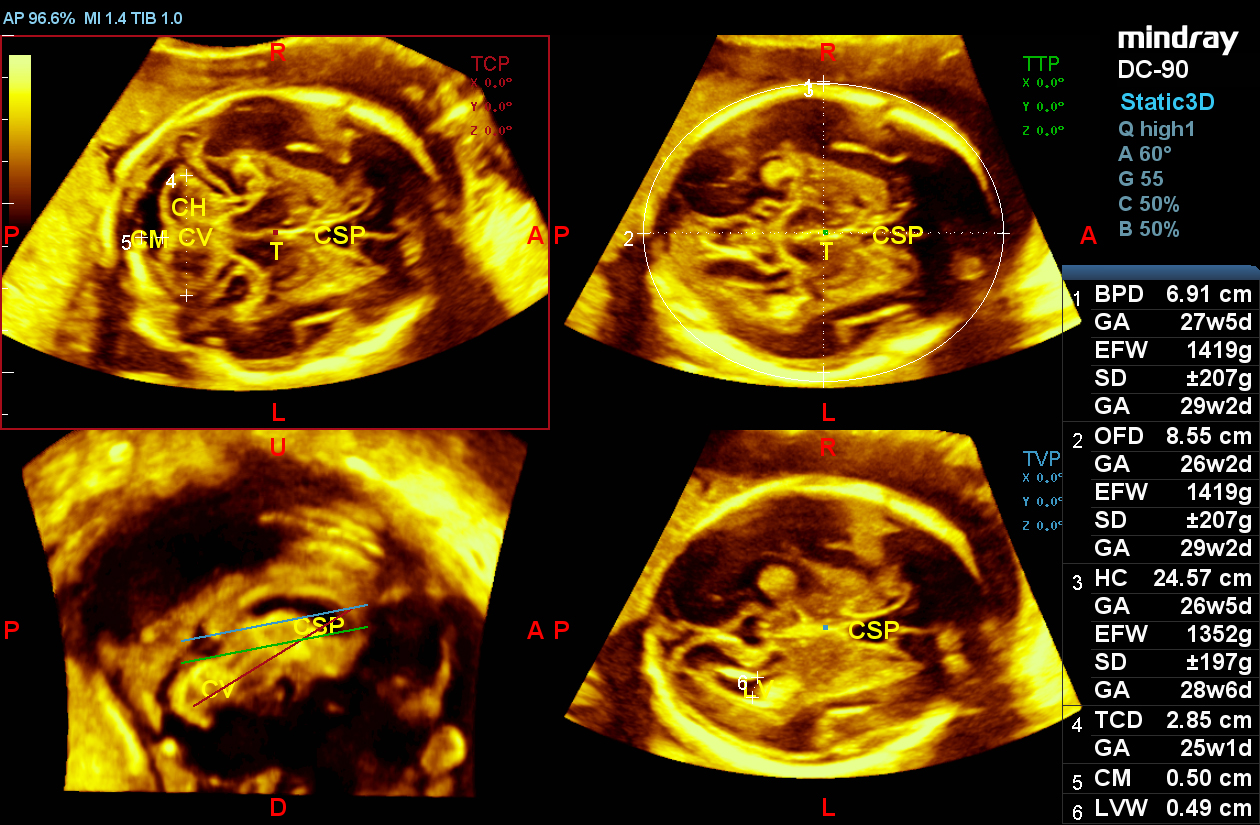

Smart Planes CNS

Smart Planes provides a robust and user-friendly solution to automatically detect planes and calculate frequently used measurements of the central nervous system (CNS) in fetal brain examinations.